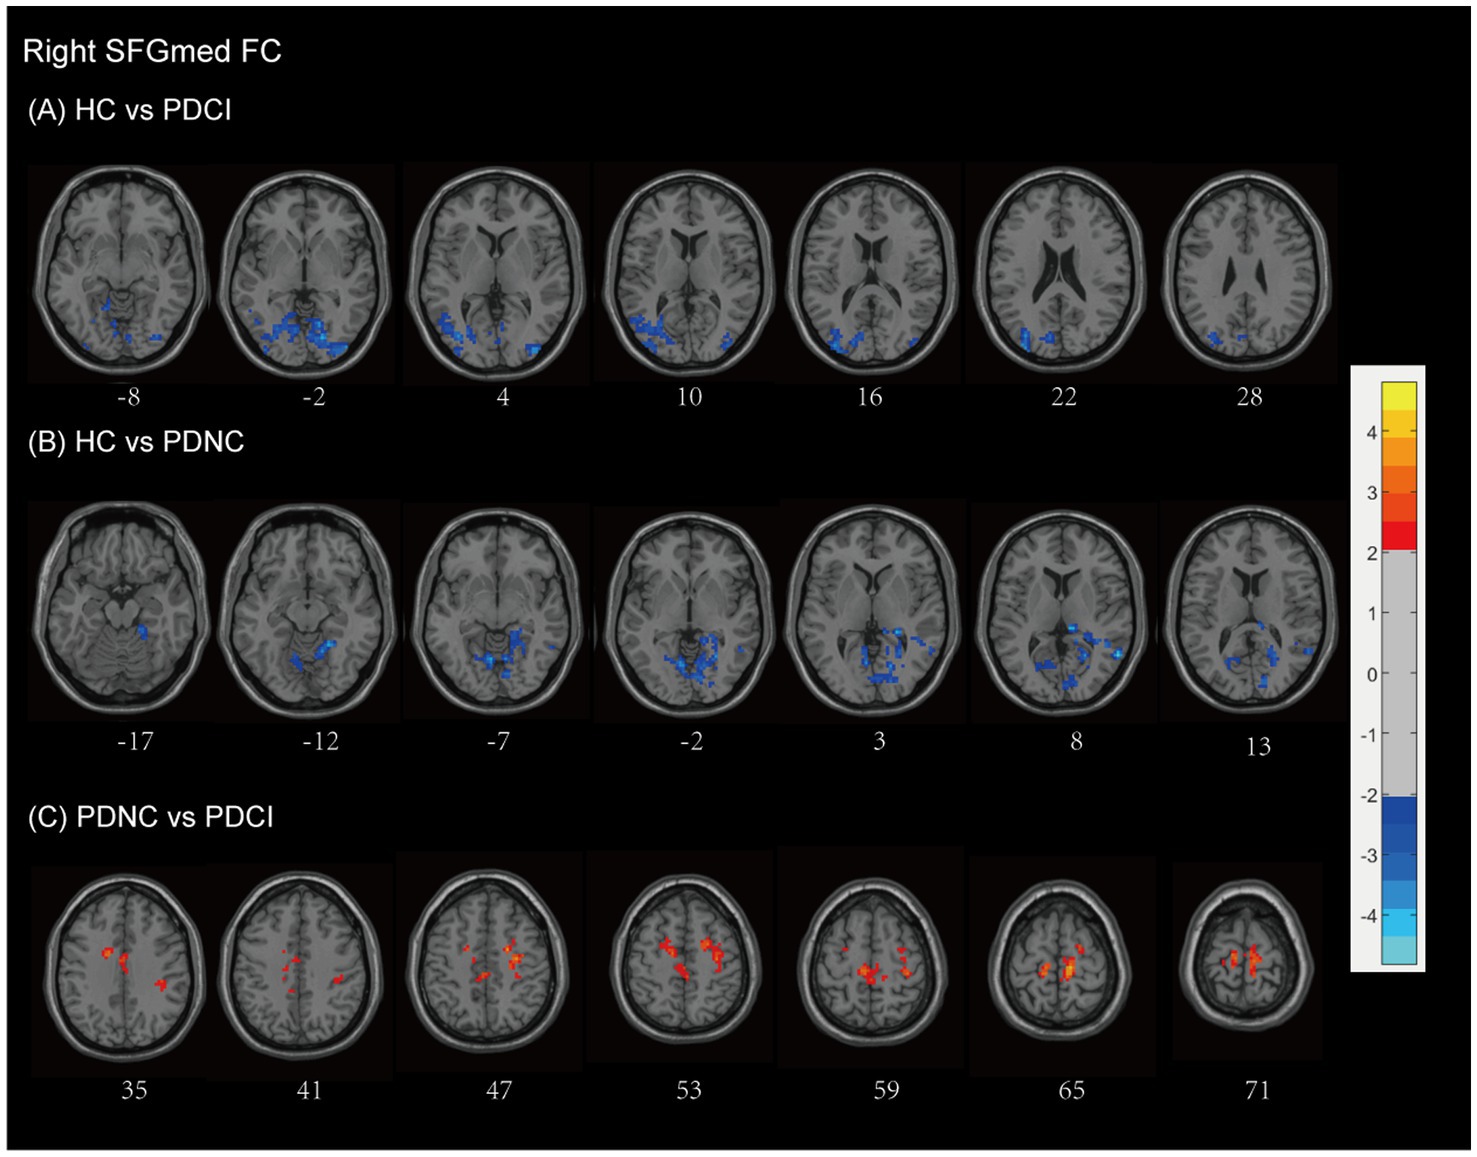

Background &Aims Forecasting specific factors influencing cognitive impairment(CI)in Parkinson's disease(PD)patients can improve clinical outcomes. This study aims to identify brain areas vulnerable to Vitamin D deficiency and assess functional integrity in PD patients with and without CI. Methods Thirty-four PD patients(14 with CI[PD-CI],20 with normal cognition[PD-NC])and 21 healthy controls(HCs) underwent serum vitamin D testing, T1-weighted MRI, and resting-state functional MRI(rs-fMRI). Voxel-based morphometry(VBM)was used to compare gray matter volume(GMV)between PD patients and HCs. Whole-brain multiple regression analyses, adjusted for age and sex, identified GMV regions associated with vitamin D levels. Resting-state functional connectivity(FC)analyses were performed using vitamin D–related regions as seeds. Correlation and multivariate regression analyses, adjusted for Hoehn and Yahr stage and age, assessed relationships among FC, cognitive performance, and vitamin D levels. Results Compared with HCs, PD patients exhibited significant GMV loss, affecting widespread brain regions including the middle frontal gyrus(MFG),superior frontal gyrus(SFG),and hippocampus. Region of interest (ROI)-based analysis revealed that Vitamin D levels were associated with GMV in the bilateral MFG and SFG (r = -0.406, P = 0.021). These findings suggest that the MFG and SFG are vulnerable regions in PD patients linked to Vitamin D levels. To assess the impact of abnormal vitamin D levels on relevant resting-state networks, clusters encompassing the bilateral SFG were used as ROIs. The intrinsic connectivity network of the vulnerable area, using the bilateral SFG as seed regions, revealed abnormal functional connectivity with several brain networks, including the visual network, the default mode network, the executive control network, the sensorimotor network, and the memory network. Abnormal FC values within the SFG functional network were associated with disease severity, cognitive dysfunction, and vitamin D levels (P < 0.05). Multi-model regression analyses revealed that connectivity in the left SFGmed network was negatively associated with CI in PD, with vitamin D levels showing a potential protective effect. Conclusion The SFG is associated with Vitamin D levels in PD patients, and disruptions in its structural and functional connectivity may link to CI. Future longitudinal studies are necessary to confirm these associations and explore the potential impact of vitamin D supplementation on cognitive function in PD.